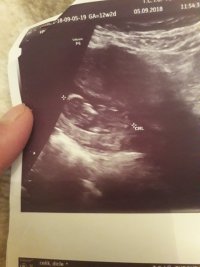

Nub teorisiyle cinsiyet tahmini bebeğim erkek mi kız mı ?

Banada yorum.yapin lutfen 12 haftaligiz

Nub teorsisi için cinsiyet tahmininde yorum isteyen arkadaşlar lütfen uyarımızı dikkate alın. Ultrason görüntüleri elinize ilk verildiği gibi net olmaz. Sık sık ışığa maruz kaldığı için görüntü kalitesi bozuluyor dolaysıyla bizlerde değerlendirme yapamıyoruz. Sizlere yorum yapabilmemiz için görüntü kalitesi aşağıdaki linkte yer alan görseller gibi olmalıdır. Ayrıca Bebeğin cinsiyeti net olarak 18-19-20. haftalarda belli olur..

Merhaba, yüklediğiniz görsellerde nub çıkıntısı anlaşılmıyor , dolaysıyla değerlendirme yapamıyoruz.. Görselin kalitesi aşağıdaki gibi olmaldır.. Sağlıklı gebelik süreci diliyorum.